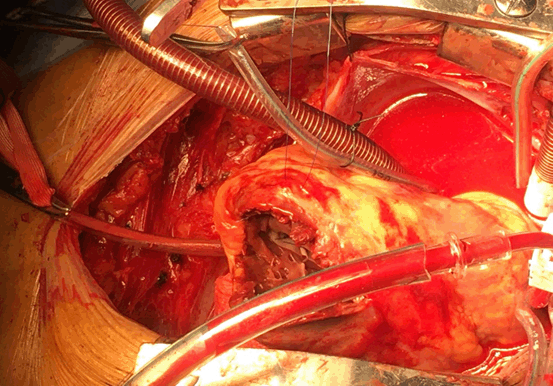

A 72-years old male complaining of sudden onset chest pain was referred to our cardiac centre. ECG was revealed acute inferior ST- segment elevation (STEMI). Relatives denied previous history of any chest pain or CCU admission. The patient was a ex-smoker, diabetic (type I), hypertension with a family history of coronary heart disease (CAD). On physical examination, the patient was restless, and distress. The blood pressure was 80/50 mm Hg, pulse 125 bpm, respiratory rate 24 bpm. His skin was cool and poorly perfused with shallow respiration, and weak peripheral pulses. Laboratory investigations were showing troponin (0.170 ng/mL), serum creatinine level (1.3 mg/dL), and MB-CK level (229 U/L). Coronary angiography was revealed total occluded left descending artery (LAD) and right coronary artery (RCA), and primary PCI was performed. Trans-Thoracic Echography (TTE) demonstrated a VSR (20 mm) located inferior basal and EF < 25% (Figures 1 and 2). Patient was in cardiogenic shock, and intra-aortic balloon pump (IABP) was inserted. Chest X-ray showed increased cardiothoracic ratio with lung congestion. Medical management is aimed to improve cardiac output and reduce shunt. Inotropes, diuretics, and IABP are often used. Patient is hemodynamically stable and still on IABP for 14-days before surgery. Heparin is stopped 6-hours before surgery.

Patient was urgently transferred to operative room. Median sternotomy, then cardiopulmonary bypass (CPB) with moderate hypothermia (32 °C) was established after cannulation of aorta, SVC, and IVC with tapes around cavae. IABP was stopped then aortic cross-clamp was placed, and antegrade blood cardioplegic arrest was induced. We made longitudinal incision lateral and parallel to left descending artery (LDA) in left ventricle infarct area. VSR identified in basal apical septum. Stay sutures were placed to expose the edges of the defect (Figure 3). The necrotic tissue was debrided, revealing a defect 2.5 cm. VSR closure without tension employed using a bovine pericardial patch with Teflon felt pledgets placed on RV (Figure 4). Ventriculotomy was closed by double layer buttressed with Teflon felt strips (Figure 5). Tisseel Lyo Sealant used after preparation by Fibrinotherm apparatus to ensure complete hemostasis (Figures 6 and 7). TTE revealed no residual shunt. Patient weaned from CPB smoothly with minimal inotropes and IABP. IABP weaned after 2 days. Patient was discharged from hospital on 10th POD without any event.

Figure 3. Intraoperative Photo showed VSR through Left Ventricular incision